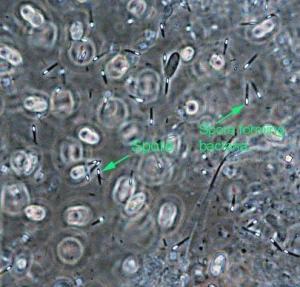

形态描述:细胞杆状,0.3~2.0μm×1.5~2.0μm,常排列成对或短链,圆的或渐尖的末端。通常多形态,幼龄时革兰氏常呈阳性,以周生鞭毛运动。芽孢椭圆或球形孢囊膨大。大多数种为化能异养菌;有的化能自养菌或无机化能营养。可以水解糖、蛋白质,或两者都无或两者皆有。它们通常从糖或蛋白胨产生混合的有机酸和醇类。不还原硫酸盐。接触酶通常阴性,专性厌氧,如在空气中生长也是极弱,生孢被抑制。它们的代谢极富多样性,最适温度10~65℃。广泛分布在环境中,许多种可产生外毒素,有的对动物有毒,由于伤口感染或吸收毒素。

杆菌属  致病菌杆菌属 致病菌(6)解释二:一属产芽孢、一般为专性厌氧、多数借周生鞭毛运动的革兰氏阳性杆菌。因其芽孢直径较大,常使细胞中间膨大呈梭状,故名。细胞大小约0.3μm×1.9μm~2μm×10μm。不能还原硫酸盐。多数过氧化氢酶阴性。化能异养,营养要求较高。一般营发酵性代谢。G+Cmol%值为22~55。广泛地分布于土壤、污泥、人和动物的肠道等处。